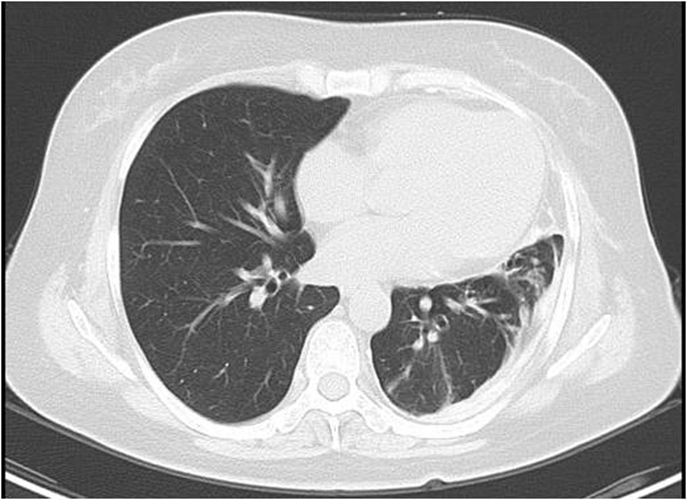

右上肺腺癌